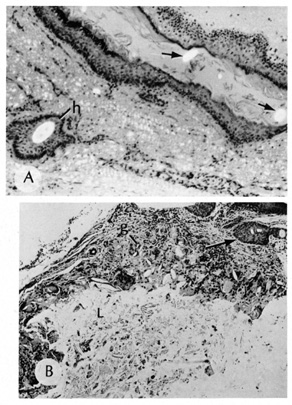

Histologically, dermoid cysts are lined by epidermis possessing various mature appendageal structures (Fig. 22). These include hair follicles with terminal hairs, sebaceous glands, eccrine glands, and, occasionally, apocrine glands.

Fig. 22. A. Dermoid cyst shows hair follicle (h) and hair shaft (arrows) in cyst lumen. B. Dermoid cyst has skin appendages in cyst wall (arrow), is lined by stratified squamous epithelium, and contains desquamated keratin in its lumen (L). There is a granulomatous inflammatory infiltrate (g) due to rupture of cyst. (From Yanoff M, Fine BS: Ocular Pathology, 3rd ed. Philadelphia, JB Lippincott, 1989, 186.)